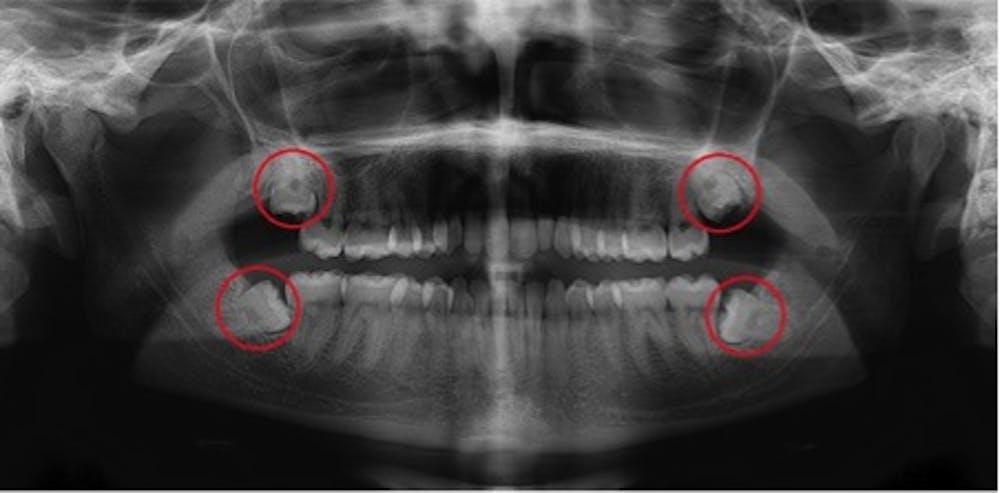

Decay stages- How advancing cavities look on x-rays. | How dentists determine when a cavity has advanced But the problem is, you don't really know what you're looking at or what to look for. When searching for a cavity on a tooth, a dentist looks for any sign on the radiograph that indicates